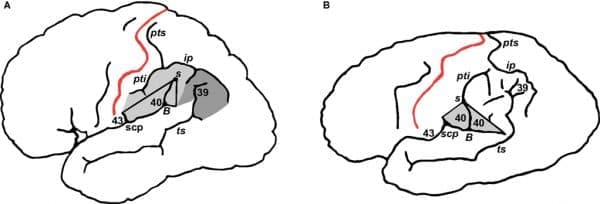

-Στην αρχική έκθεση του 1985,

ο Χάρβεϊ και οι συνεργάτες του διαπίστωσαν ότι στην περιοχή Brodmann Area 39 -μια περιοχή όπου συναντώνται ο κροταφικός, ο βρεγματικός και ο ινιακός λοβός- η αναλογία νευρώνων προς γλοία του Αϊνστάιν ήταν σημαντικά μικρότερη από ό,τι ήταν στην ίδια περιοχή σε 11 άλλους εγκεφάλους ελέγχου.

Αλλά η ομάδα ελέγχου δεν ήταν τόσο ευρεία: Οι εγκέφαλοι προέρχονταν από άτομα ηλικίας 47 έως 80 ετών, ενώ ο Αϊνστάιν πέθανε σε ηλικία 76 ετών. Οι εγκέφαλοι ελέγχου ήταν επίσης φρέσκοι, ενώ ο

-Το 1999, ο Χάρβεϊ

και οι Καναδοί συνεργάτες του έβαλαν τον εγκέφαλο του Αϊνστάιν σε ένα από τα πιο έγκυρα ιατρικά περιοδικά του κόσμου, το The Lancet. Βασιζόμενοι σε παλιές φωτογραφίες που είχαν ληφθεί από τον εγκέφαλο του Αϊνστάιν πριν αυτός κοπεί, οι ερευνητές ισχυρίστηκαν ότι ο Αϊνστάιν είχε ένα ανώμαλο μοτίβο αναδίπλωσης σε μέρος του βρεγματικού λοβού του, μια περιοχή που έχει συνδεθεί με τη μαθηματική ικανότητα. Ανέφεραν επίσης ότι οι βρεγματικοί λοβοί του ήταν κατά 15 τοις εκατό ευρύτεροι και πιο συμμετρικοί από εκείνους των εγκεφάλων της έρευνας. Για άλλη μια φορά, όμως, οι ερευνητές γνώριζαν ποιες φωτογραφίες έδειχναν τον εγκέφαλο του Αϊνστάιν.